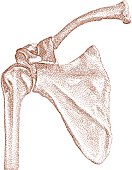

אנטומיה-מבנה הכתף: מבנה העצמות

נביט במבנה הגרמי של פרק הכתף: אנו מבחינים בשלש עצמות: עצם הזרוע, (אנכית) בחלקו השמאלי של האיור. עצם השכמה המשולשת באמצע, ועצם הבריח בחלקו העליון של האיור המתחברת אל השכמה בחלקה העליון. בין השכמה לזרוע קיים פרק סחוסי ונייד הנקרא glenohumeral joint. זהו הציר המאפשר את תנועת הזרוע בכל הכיוונים. מעליו, פרק קטן יותר, acromioclavicular joint התוחם את החלק העליון של הפרק וקובע את חיבורו לעצמות החזה.

נביט במבנה הגרמי של פרק הכתף: אנו מבחינים בשלש עצמות: עצם הזרוע, (אנכית) בחלקו השמאלי של האיור. עצם השכמה המשולשת באמצע, ועצם הבריח בחלקו העליון של האיור המתחברת אל השכמה בחלקה העליון. בין השכמה לזרוע קיים פרק סחוסי ונייד הנקרא glenohumeral joint. זהו הציר המאפשר את תנועת הזרוע בכל הכיוונים. מעליו, פרק קטן יותר, acromioclavicular joint התוחם את החלק העליון של הפרק וקובע את חיבורו לעצמות החזה.